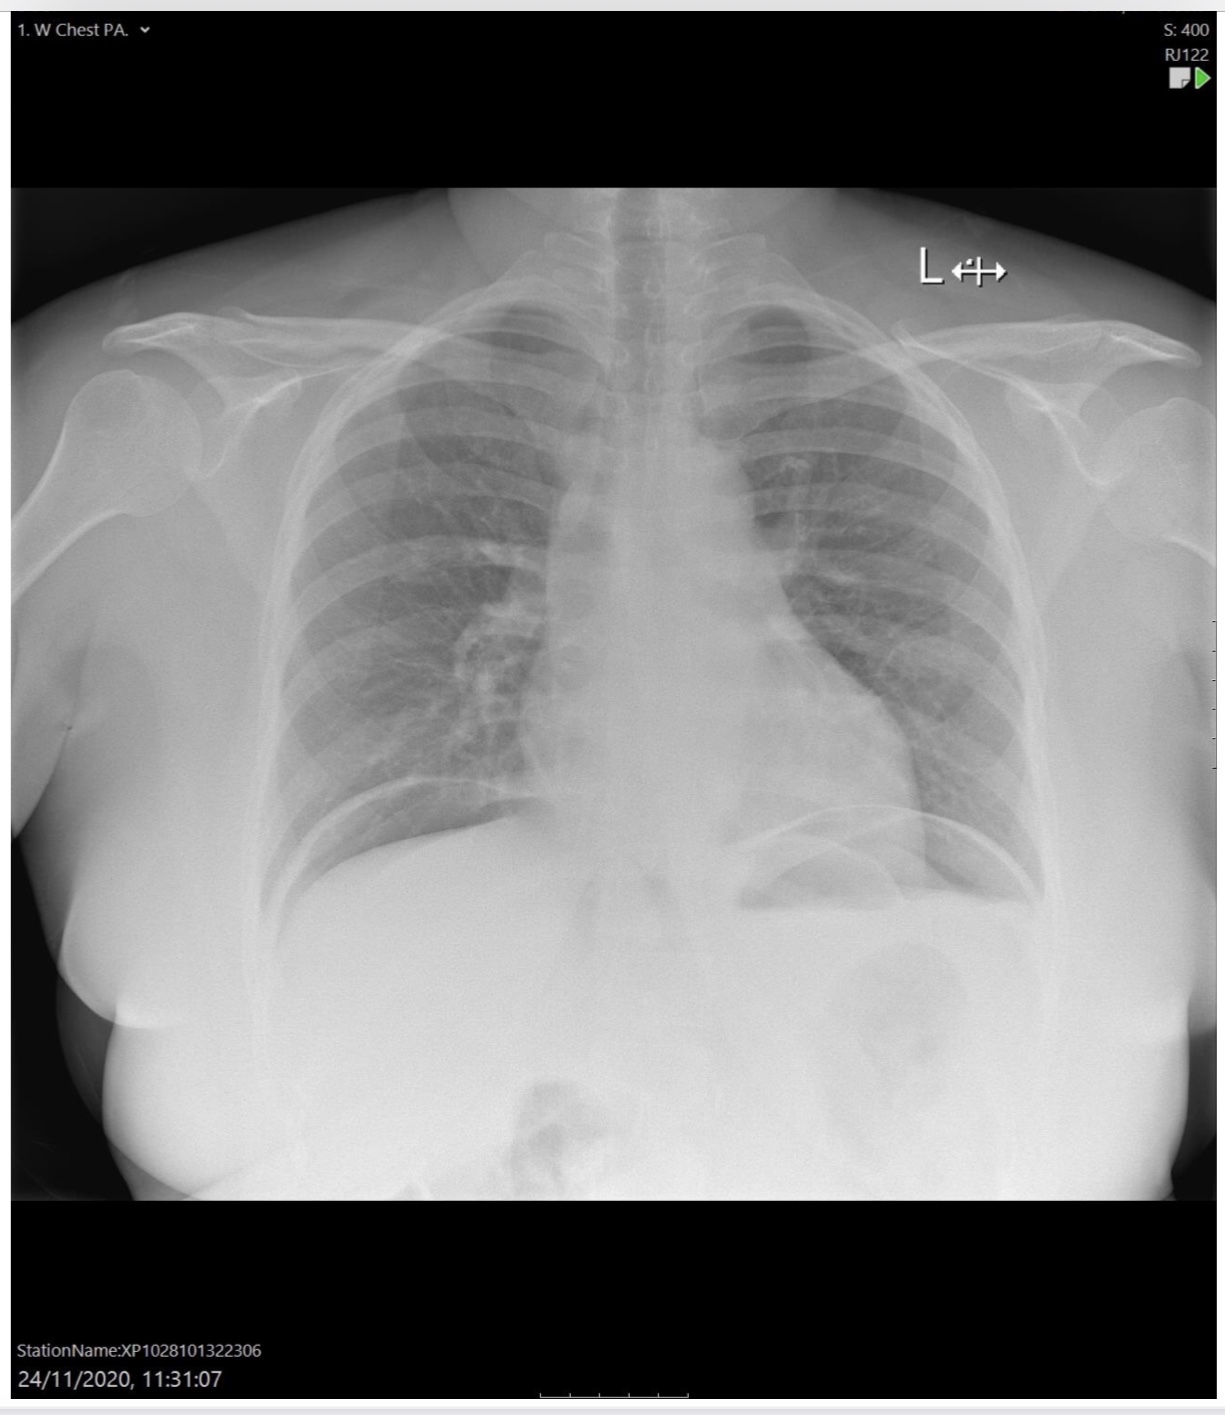

Heart failure

Alveolar oedema

Kerley B lines

Cardiomegaly

Dilated upper lobe vessels